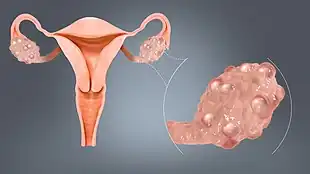

| A polycystic ovary | |

- Polycystic ovaries: PCOS is a complicated disorder characterized by high androgen levels, irregular menstruation, and/or small cysts on one or both ovaries. Ovaries might get enlarged and comprise follicles surrounding the eggs. As result, ovaries might fail to function regularly. This disease is related to the number of follicles per ovary each month growing from the average range of 6-8 to double, triple or more. Women with PCOS have higher risk of multiple diseases including Infertility, type 2 diabetes mellitus (DM-2), cardiovascular risk, metabolic syndrome, obesity, impaired glucose tolerance, depression, obstructive sleep apnea (OSA), endometrial cancer, and nonalcoholic fatty liver disease/nonalcoholic steatohepatitis (NAFLD/NASH).[36]

The syndrome acquired its most widely used name due to the common sign on ultrasound examination of multiple (poly) ovarian cysts. These "cysts" are in fact immature ovarian follicles. The follicles have developed from primordial follicles, but this development has stopped ("arrested") at an early stage, due to the disturbed ovarian function. The follicles may be oriented along the ovarian periphery, appearing as a 'string of pearls' on ultrasound examination.[86]

Most common names for this disease derive from a typical finding on medical images, called a polycystic ovary. A polycystic ovary has an abnormally large number of developing eggs visible near its surface, looking like many small cysts.[91]